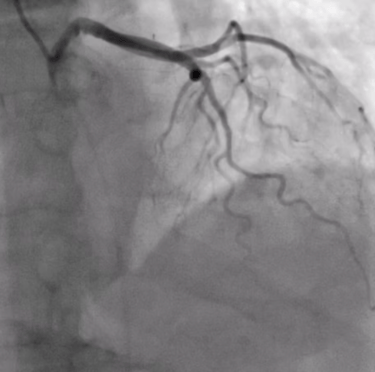

Invasive coronary angiography is a procedure that uses contrast dye and X-rays to visualise the heart’s arteries, assessing for blockages. It is performed under local anaesthesia, typically via wrist access, to guide treatment decisions for coronary artery disease.

Coronary Angioplasty and stenting are minimally invasive procedures used to treat blocked or narrowed heart vessels. The procedure involves inserting a thin catheter with a balloon into the affected artery, usually via the wrist (radial) or groin (femoral) artery, under local anaesthesia. The balloon is inflated to widen the artery, and a stent (a small metal mesh tube) is placed to keep it open, restoring blood flow. The goal is to relieve chest pain (angina), improve heart function, and reduce the risk of heart attacks.